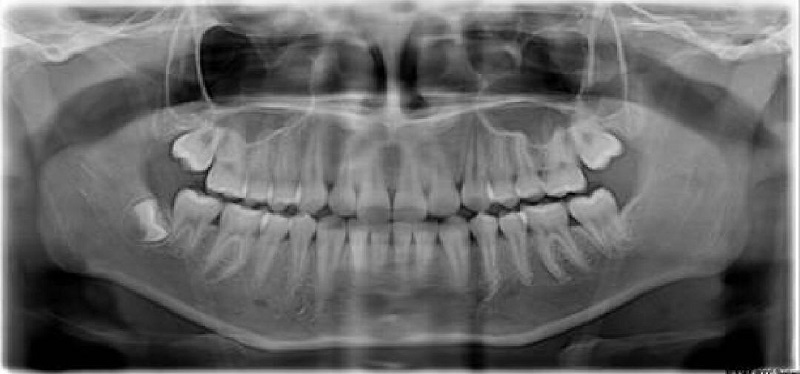

全景片(曲面斷層片)